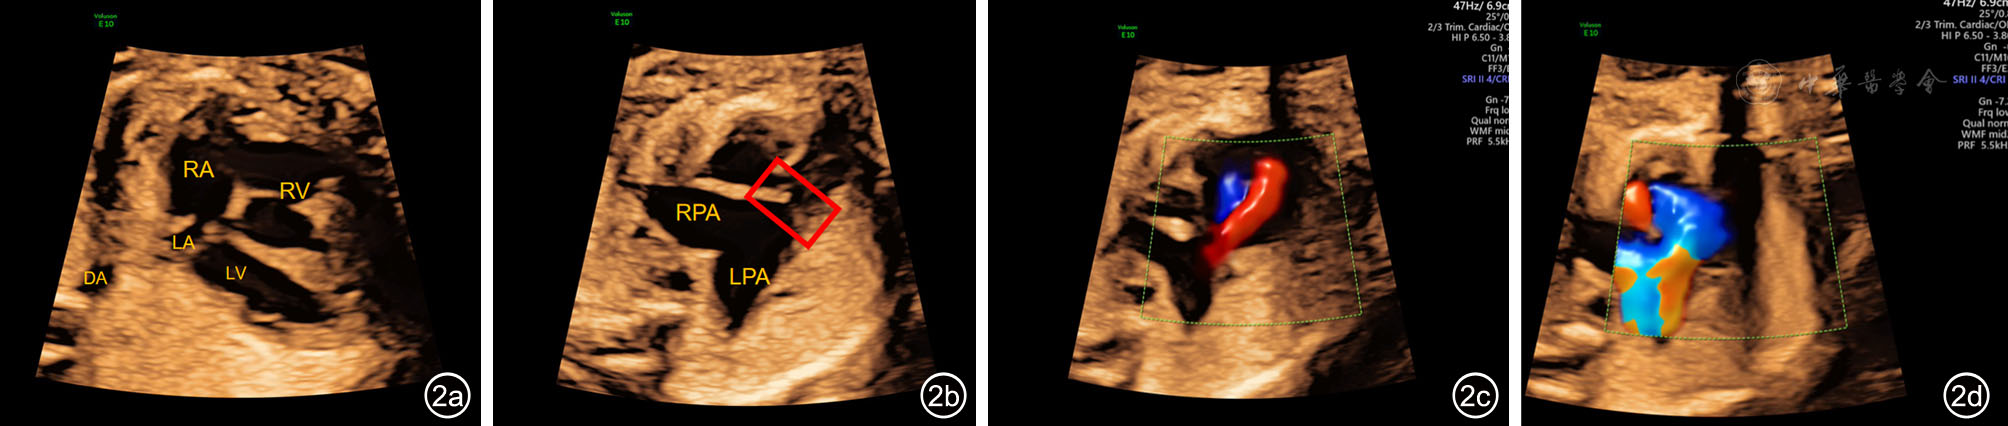

2.测量标准911:在收缩末期的标准四腔心切面,经过胎儿心脏十字交叉和DA的中点画一条线,沿线测量LA后壁外侧缘至DA前壁外侧缘的距离(PLSA)、DA前壁内侧缘至后壁内侧缘的距离(DA内径)。每个参数均测量三次取平均值,单位mm。PLASI=PLSA/DA内径(图1)。

图1 标准四腔心切面左心房后间隙(PLAS)测量超声图像。图a为正常胎儿;图b为肺动脉瓣缺如综合征胎儿[图中黄色线段1为PLAS,红色线段2为降主动脉(DA)内径,左心房后间隙指数(PLASI)=PLAS/DA内径]

注:LA为左心房;LV为左心室;RA为右心房;RV为右心室;DA为降主动脉